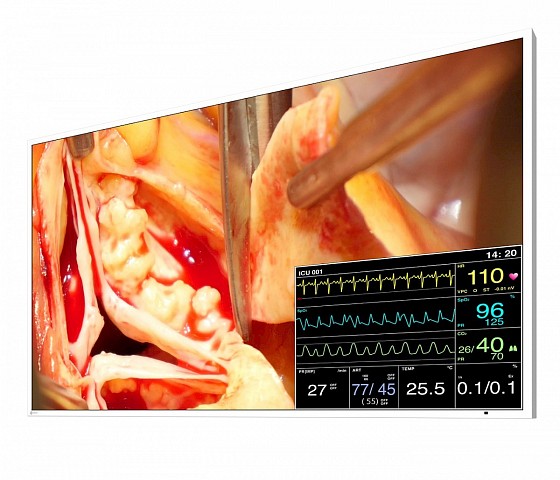

This 49” widescreen monitor is ideally suited for viewing medical images under OR conditions. Numerous input and output signals, image combination capabilities, and gamma models pre-calibrated at the factory enable its use within the widest range of applications. With its fan-free design and water-tight, easy to clean front, the monitor is perfectly suited for sterile hospital environments.

- Flexible image arrangement thanks to the Picture-in-Picture (PiP) and Picture-at-Picture (PaP) functions